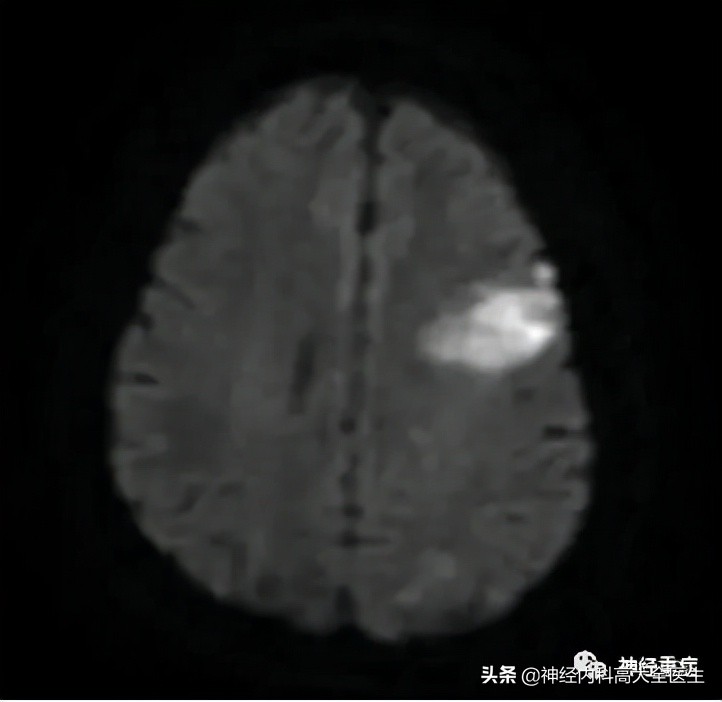

典型疾病如急性脑梗死早期: